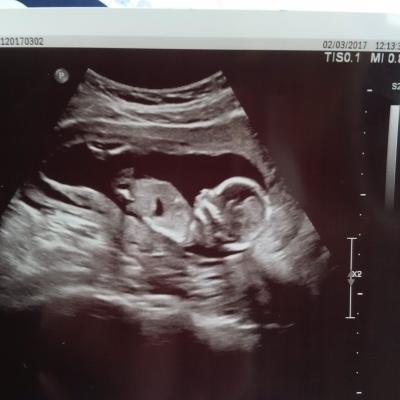

Huhu, bei uns sieht alles wunderbar aus! Unser kleiner mensch ist 100g schwer und ca 13 cm lang hat alles da wo es sein soll! :) ich bin jetzt sehr happy und beruhigt... Hatte etwas Angst wir waren jetzt 10 tage in Ägypten aber unserem Baby war das fliegen rumfahren und Wetter Umstellung anscheinend egal :)) was Geschlecht angeht war noch nichts zu sehen, der nächste Termin ist am 07.04 und da werden wir es zu 100% erfahren da kann es auch endlich losgehen mit shoppen! :) zur zeit haben wir 2 schränke für unsere Küche nach bestellt und heute kommen noch Regale dazu, der stolze Papa will sich beweisen anbei unser Glück :)

Bild zu zurück vom baby tv :) - Forum für August - Mamis